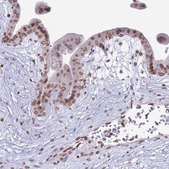

Application:

IF, IHC

immunofluorescence: 0.25-2 μg/mL, immunohistochemistry: 1:50-1:200

All Prestige Antibodies Powered by Atlas Antibodies are developed and validated by the Human Protein Atlas (HPA) project and as a result, are supported by the most extensive characterization in the industry.

The Human Protein Atlas project can be subdivided into three efforts: Human Tissue Atlas, Cancer Atlas, and Human Cell Atlas. The antibodies that have been generated in support of the Tissue and Cancer Atlas projects have been tested by immunohistochemistry against hundreds of normal and disease tissues and through the recent efforts of the Human Cell Atlas project, many have been characterized by immunofluorescence to map the human proteome not only at the tissue level but now at the subcellular level. These images and the collection of this vast data set can be viewed on the Human Protein Atlas (HPA) site by clicking on the Image Gallery link. We also provide Prestige Antibodies® protocols and other useful information.

• IHC tissue array of 44 normal human tissues and 20 of the most common cancer type tissues.